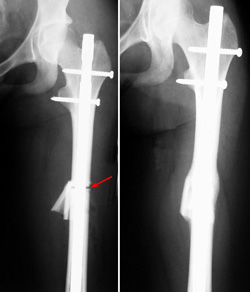

In patients who are finished growing, the longer limb can sometimes be shortened to even out the leg lengths.

To do this, the doctor removes a section of bone from the middle of the longer limb, then inserts metal plates and screws or a rod to hold the bone in place while it heals.

Because a major shortening may weaken the muscles of the leg, limb shortening cannot be used for significant limb length discrepancies. In the femur (thighbone), a maximum of 3 inches can be shortened. In the tibia (shinbone), a maximum of 2 inches can be shortened.

(Left) In this x-ray, a section of bone has been removed to shorten the femur (arrow). A rod has been inserted to hold the bone in place during healing. (Right) After four months, the gap between the pieces of bone has healed.

Reproduced from Song K (ed): Orthopaedic Knowledge Update Pediatrics 4. Rosemont, IL. American Academy of Orthopaedic Surgeons, 2011, p. 226.